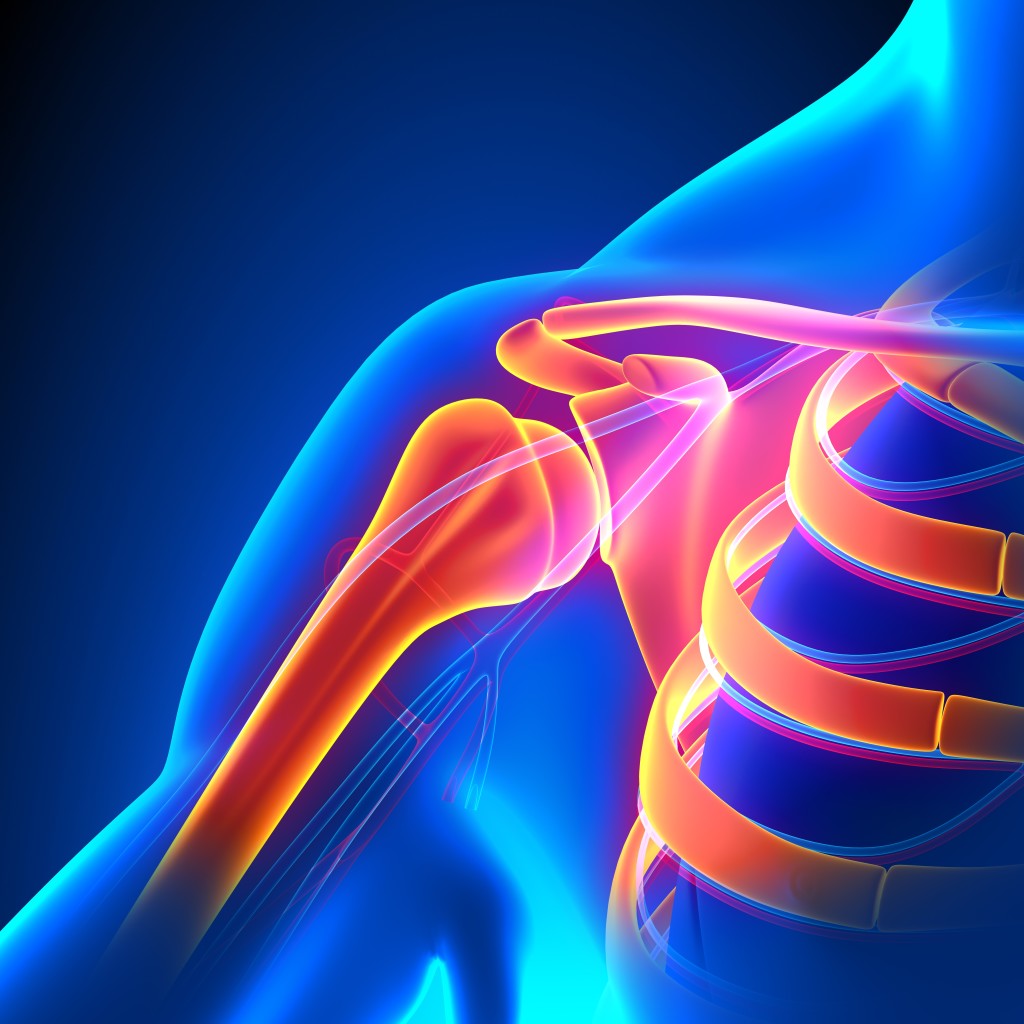

Анатомические рисунки суставов человека